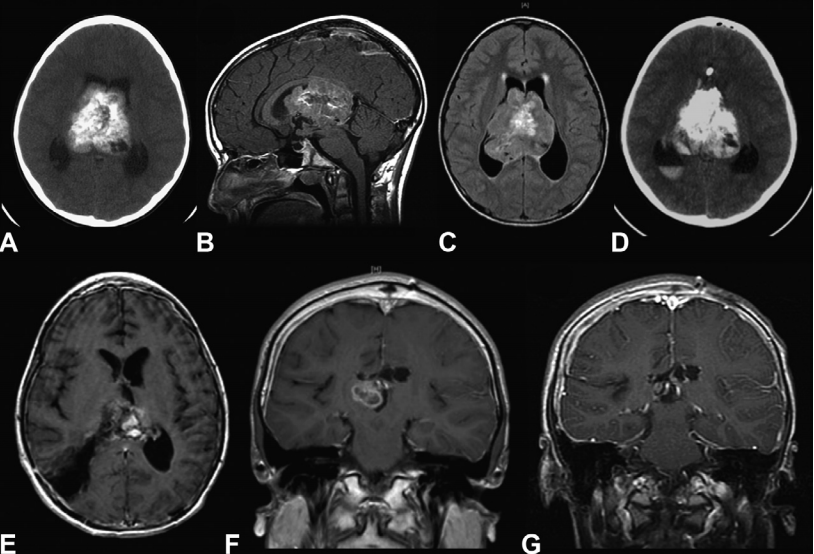

12岁男孩,因出现近3周的头痛和急性恶化而入院治疗。(A)颅脑CT显示一个大的脑室内肿块伴钙化和瘤内出血并伴有脑积水。(B, C)磁共振成像(MRI)显示一个可能起源于透明隔的异质性强化肿瘤,填充在侧脑室和三脑室的大部分区域。(D)尝试左额半球间经胼胝体切除术后的CT扫描显示脑室内和腔内内出血。(E)二次手术,经右顶叶经皮质入路行次全切除术,术后T1增强MRI为WHO 2级室管膜瘤,病人进行局部放疗。(F)术后增强MRI显示肿瘤再次生长,因此在部分切除后再次放疗。(G)随访图像显示6年后病情稳定。